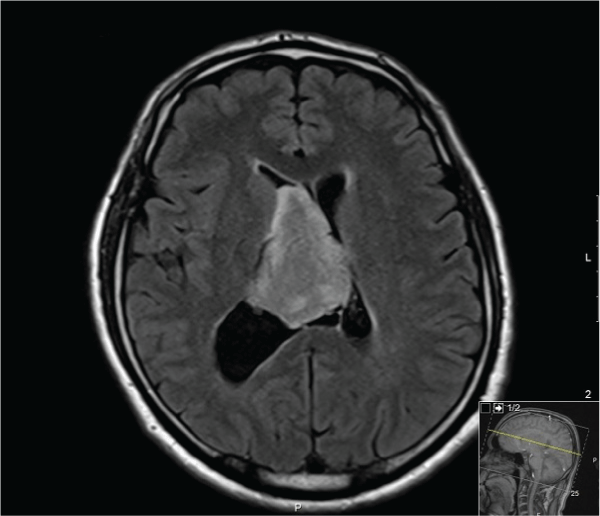

A 40-year-old man presenting with headache and dizziness of several months duration was found to have a large intraventricular mass during the clinical workup (Figure 1). A stereotactic biopsy of the mass revealed cellular neoplastic tissue with monotonous round cells (Figure 2). There was not any mitotic activity, necrosis, pleomorphism, microvascular proliferation (Figure 3). Immunohistochemical staining revealed negative staining with leucocyte common antigen (LCA) (Figure 4) and glial fibrillarey acidic protein (GFAP) (Figure 5) in the neoplastic cells. However there was diffuse and strong synaptophysin positivity (Figure 6). These pathologic findings pointed to a central neurocytoma (CN) as outlined in the recent monograph of World Health Organization [1].

Figure 1: Magnetic Resonance Image (MRI): Axial non-contrast image showing a large relatively homogeneous intraventricular mass about 6 cm in greatest dimension.